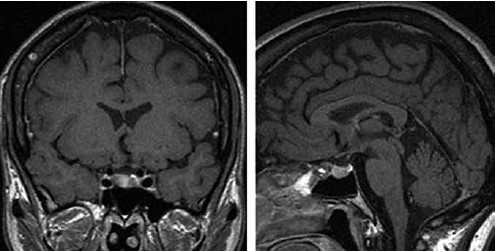

Mulher de 33 anos se apresenta no ambulatório devido a dores de cabeça e visão embaçada. Ela não tem histórico de enxaqueca, mas teve alguma lactação recente junto com um ciclo menstrual tardio. O teste de gravidez é negativo. A ressonância magnética encefálica realizada é mostrada a seguir.

(Arquivo pessoal; imagens usadas com autorização)

Considerando a principal hipótese diagnóstica, é correto afirmar que